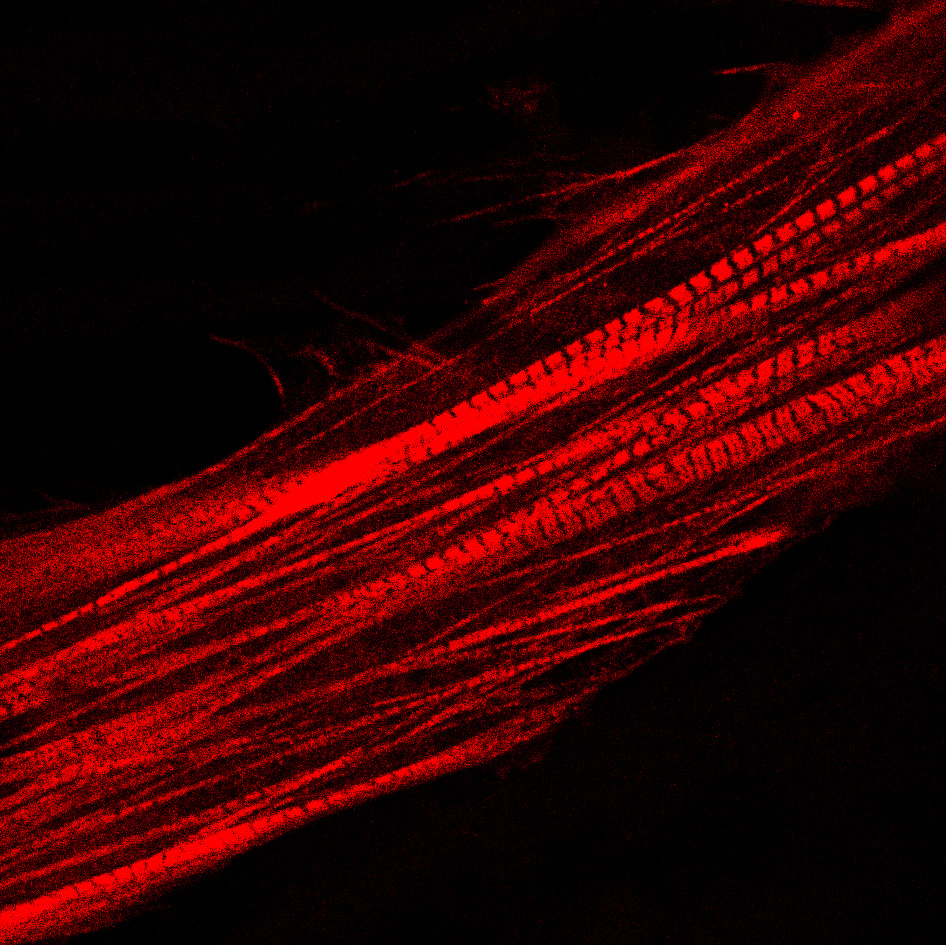

EEC is a severe newborn condition within the uro-rectal congenital malformation spectrum impacting continence, sexual and renal function. MyoPax’s cell therapy uses patient-specific muscle stem cells, harnessing their regenerative potential through a proprietary and patented stem cell technology to repair the patient’s urinary sphincter muscle defect.